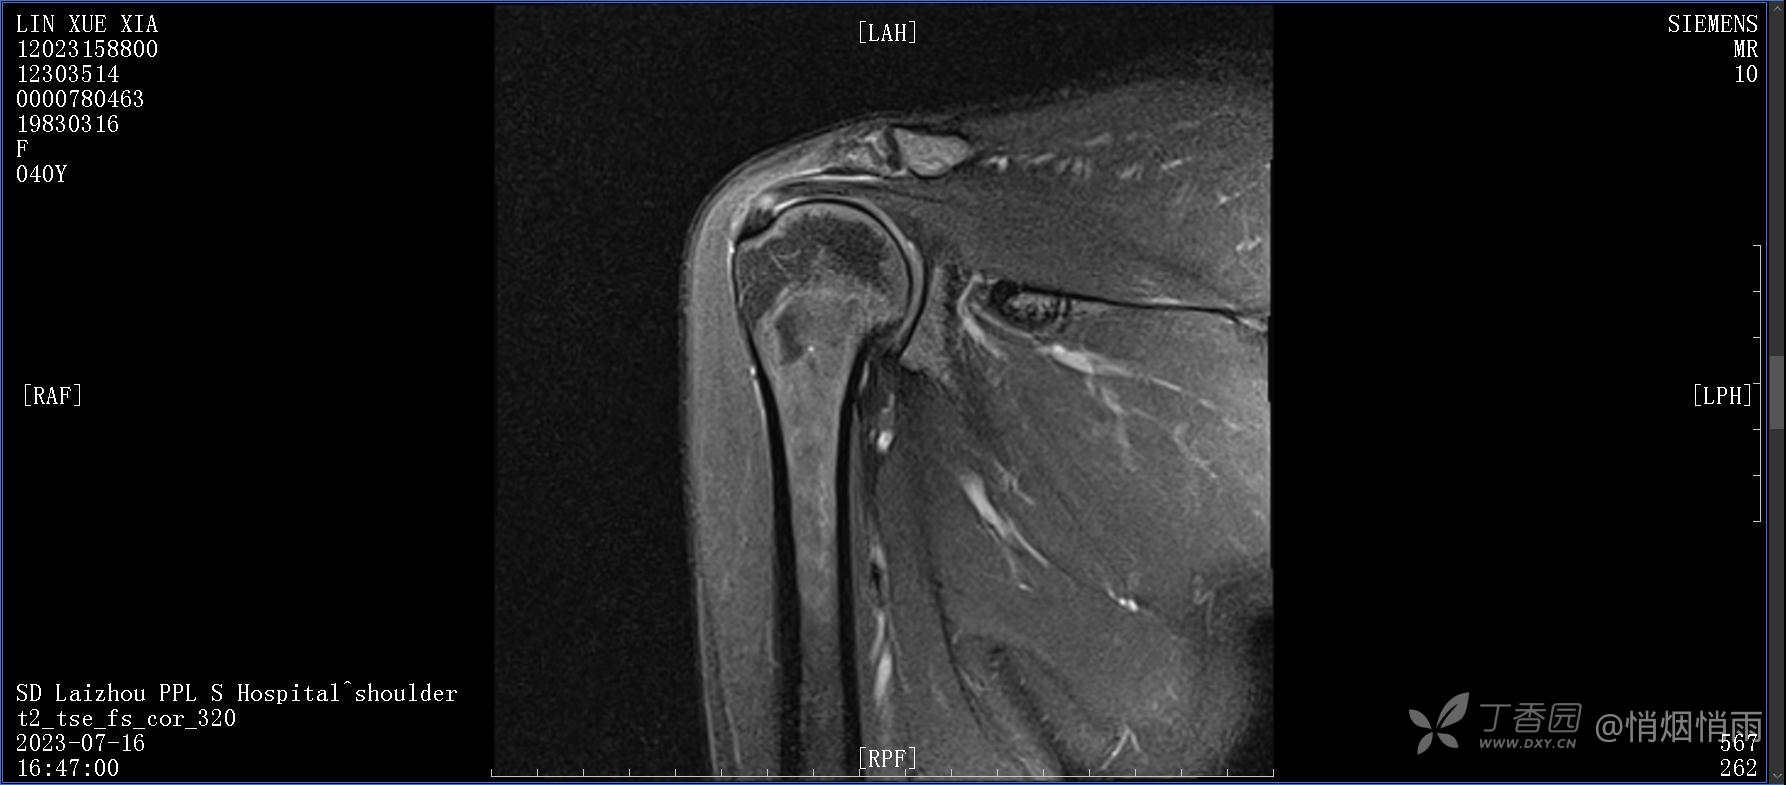

查体:右肩关节局部轻度肿胀,肩胛区压痛明显,痛处不固定,肩关节痛性活动受限,jobe test(+),lift -off test(+),中指、环指感觉较余指减退,余肢端感觉及血运情况可。

目前的诊断,暂时依据辅助检查诊为肩袖损伤,但是患者疼痛的性质和特点,却不是单纯的肩袖损伤所致。考虑过胸廓出口综合征,但是该疾病会出现肩胛区的疼痛吗?(由于考虑到费用的问题,没再进行下一步的检查)带状疱疹会有如此的症状吗?